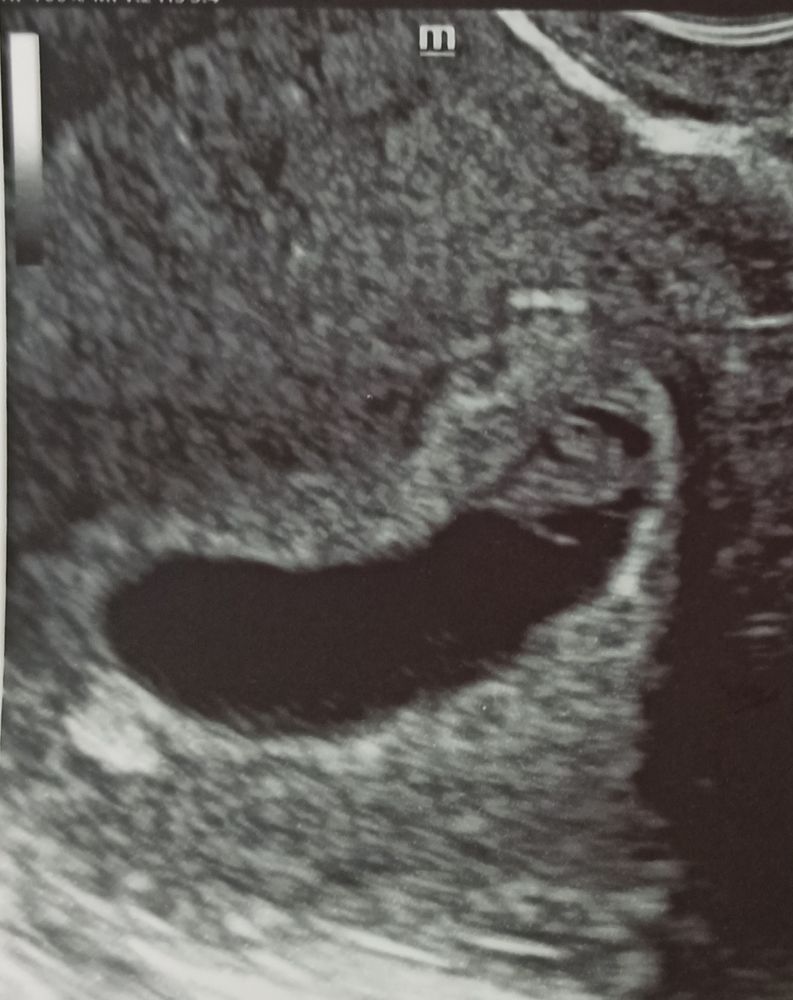

УЗИ на 34 дпо (6+6) ❤🤞🤞🤞

Сходили на УЗИ вместе с мужем, он счастлив🥰 сегодня 20 марта на 34 дпо (6+6):

ПЯ 25 мм, ЖМ 3 мм, КТР 9 мм, ЧСС 141 уд/мин, киста ЖТ 41*36 мм. Врач сказал, что прикрепление плаценты по передней стенке в центре в дне матки, так что не знаю как по методу Рамзи смотреть, по фото плацента сверху слева, может мальчик👦❤ это было бы здорово 👍 Позже сдам анализ на определение пола плода по крови матери. Токсикоз продолжается: тошнит от голода, после еды тяжесть и отрыжка, приходится есть каждые 2 часа понемногу, надеюсь ещё недельку и пройдëт, как и в другие беременности токсикоз был с 5 по 8 неделю, сейчас хочется мясное, острое, солёное, кислое, а вот на сладкое не тянет, может позже вернётся тяга к сладостям. Хотела посмотреть прогестерон и до кучи для архива сдала сегодня и ХГЧ: